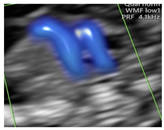

Figure 1.

Case of disagreement in the characterization of color Doppler pattern on the 3VTV between operators 1 and 2 in a case of Ebstein anomaly at 12 + 6 weeks’ gestation. (A,B) show different frames of a videoclip of the 3VTV. (A) Operator 1 observed an abnormal 3VTV pattern in terms of “abnormal vessel number”; (B) operator 2 characterized the same case as with “abnormal vessel dimensions”. AoA, aortich arch; T, trachea; arrow, small pulmonary artery.